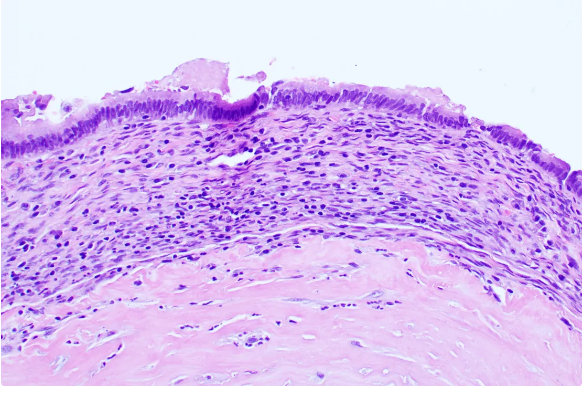

This is an incidental finding overlying an anal fibroepithelial polyp.  It is termed "pagetoid dyskeratosis" but it is simply reactive.  The same finding is known in prolapsed uterine cervices. A few GI Survival Guides are still around.  Try innovativesciencepress.com